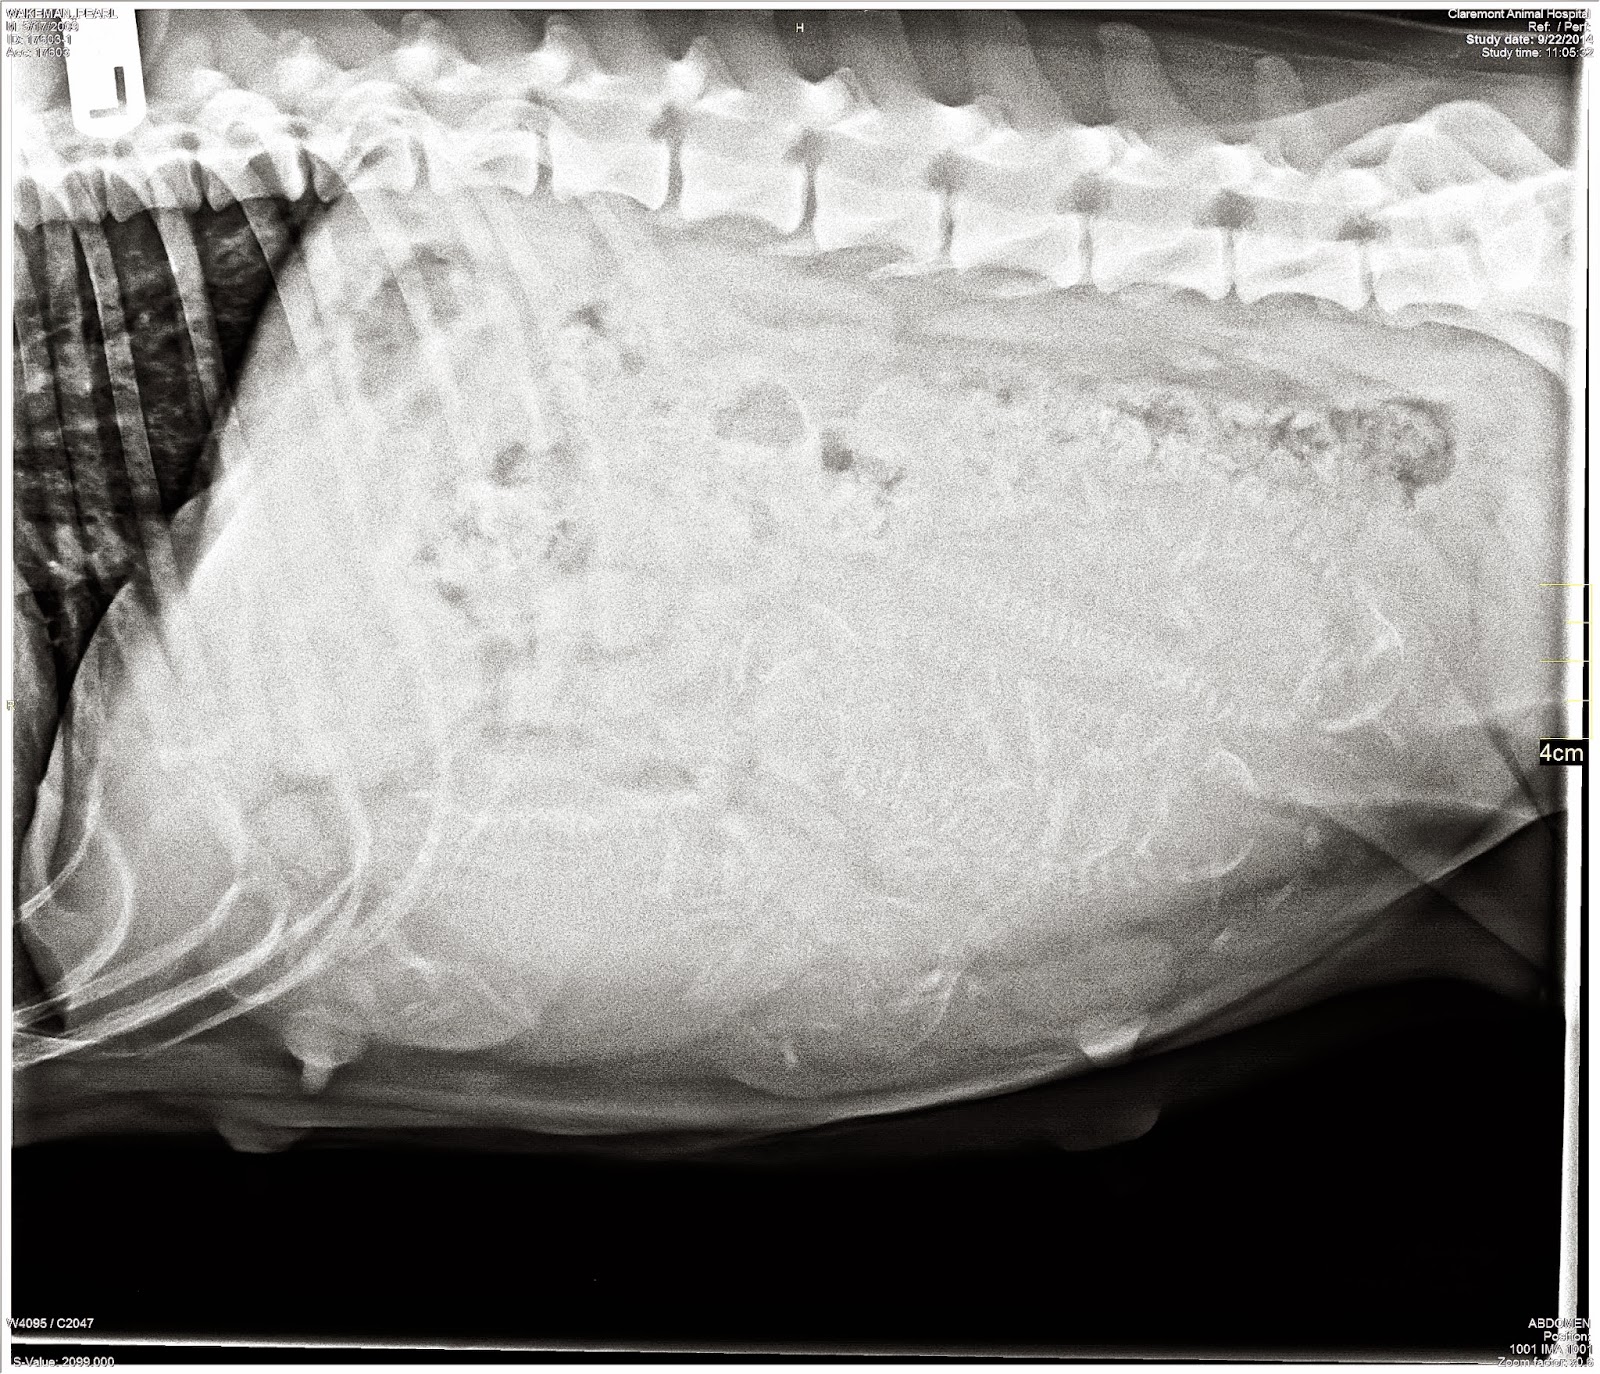

An Xray was taken on 9/22/14 - 50 days into pregnancy

The vet counts 5 puppies - hard to read, they are there.

Last time, 2011 litter, the vet counted around 6 or 7 and there were 9, so

who knows... 5 is good :)